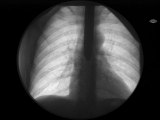

SWORD SWALLOWING by Dr. Gertes

A solid stainless metal sword was swallowed.